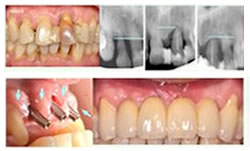

La segunda fase consiste en la construcción del diente o dientes de remplazo (prótesis). Cuando el periodo de curación haya terminado, su dentista descubrirá la parte superior del implante dental usando un procedimiento rápido y sencillo. Entonces, usará el implante como la base sólida para restaurar sus dientes.

Su dentista recomendará el tipo de restauración que sea mejor para usted. Las opciones incluyen coronas para reemplazar un solo diente, puentes cuando faltan varios dientes y dentaduras fijas. Cada opción será evaluada cuidadosamente para su caso individual.

La reciente aparición de implantes de diseño anatómico evolucionado, sumada a los cambios biológicos propuestos que incluyen la colocación de los mismos a un mínimo torque para su fijación inicial, la no realización de incisiones ni de colgajos de tejidos blandos y la inexistente necesidad de realizar puntos de sutura, brindan una mejora notable en la respuesta posquirúrgica del paciente.

Por todo esto, hoy en día nos acercamos al ideal que desea todo paciente: extraer un diente y colocar en su sitio un implante que se comporte en el largo plazo como un diente natural, haciendo de este modo altamente predecibles los resultados clínicos obtenidos, y permitiendo dar respuestas a casos considerados hasta ahora como inviables, que se resolvían por medio de prótesis removibles que generaban gran disconformidad funcional, estética y psicológica en los pacientes.